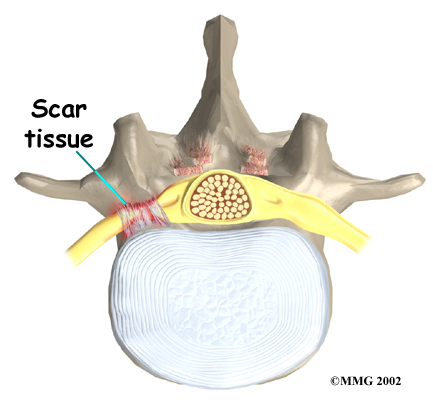

Any surgery that is done near the spinal canal can potentially cause injury to the spinal cord or spinal nerves. Injury can occur from bumping or cutting the nerve tissue with a surgical instrument, from swelling around the nerve, or from the formation of . An injury to these structures can cause muscle weakness and a loss of sensation to the areas supplied by the nerve.